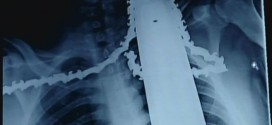

James Valentine, a 21-year old Pennsylvania man survived a chainsaw accident that could have killed him. Instead, 30 stitches and an hour of surgery later and a day after the accident, Valentine was recovering in stable condition at a Pennsylvania hospital.